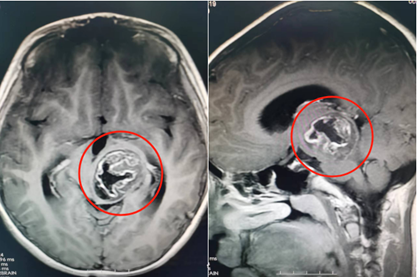

脑部检查结果提示,轩仔的左侧丘脑、中脑存在占位性病变,大小约为39mm×30mm×35mm。该院副院长鲁明在接诊时,发现患儿左眼斜视明显、右上肢肌力下降,推断是脑肿瘤引起的症状。

术前影像资料

完善术前检查,鲁明带领该院神经外五科手术团队为患儿行脑肿瘤切除手术。术后病理诊断为毛细胞星形细胞瘤I级。